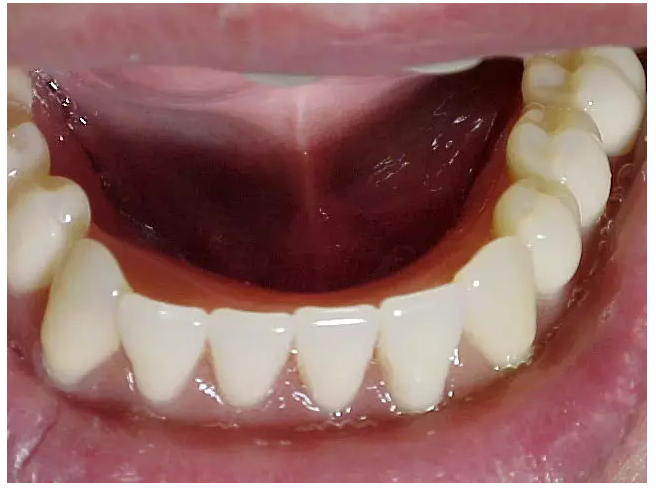

醫(yī)生在為患者制取印模之前,必須先對(duì)患者口腔的內(nèi)外環(huán)境進(jìn)行一個(gè)系統(tǒng)的檢查,包括患者現(xiàn)有的義齒、牙槽嵴的情況、粘膜的情況、唇頰舌肌和舌體情況、顳下頜關(guān)

節(jié)的情況等等。通過觀察,醫(yī)生要明確印模的輪廓,未來基托以及牙列的輪廓。并且要在義齒設(shè)計(jì)單上標(biāo)注有關(guān)的信息,讓技師的操作更明朗化。

尤其是口內(nèi)的檢查,應(yīng)當(dāng)仔細(xì)的檢查和觸診,對(duì)技師確定基托的范圍和厚度、需要緩沖和伸展的區(qū)域做明確的描述。

特別是有些牙槽嵴吸收嚴(yán)重的患者,此時(shí)患者的前庭顯得相當(dāng)?shù)膶?,醫(yī)生應(yīng)當(dāng)記錄下見到的情景,讓技師在操作時(shí)做到心中有數(shù)。

如果有條件的話,可以讓技師參與患者的初診,讓技師更直觀的了解患者的面容、膚色、口唇的形態(tài)、口腔內(nèi)軟硬組織的情況,原來義齒的佩戴情況等有關(guān)的信息,了解患者對(duì)義齒的期望。

還可以通過照片的形式,讓技師直觀地了解患者有關(guān)的信息。